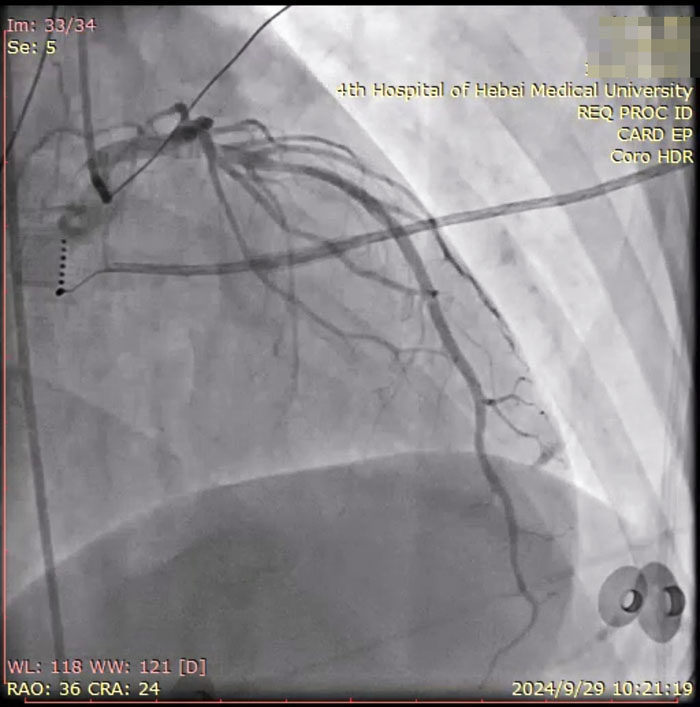

由于患者症状加重,姚铁柱副主任决定尽早为患者行电生理检查+射频消融术。在积极完善术前检查过程中,患者冠脉CTA结果回报:CTA成像符合动脉粥样硬化表现,左前降支中段非钙化斑块伴管腔重度狭窄。姚铁柱副主任再次认真查看患者病例后决定同时行冠脉造影术及心电生理检查+射频消融术。

手术当日,医护人员连接多导电生理仪和CARTO三维标测系统,对病人进行术前消毒,局麻后穿刺股静脉,操作ST消融导管至右房,建立右心三维解剖。术中,姚铁柱副主任操作ST消融导管经三尖瓣进入右室流出道,于右室流出道后游离壁标测到最早激动靶点,诱发室早形态与原体表心电图室早形态相同,给予放电消融,患者室早消失;继续行冠脉造影术,导管造影结果显示,前降支中段可见约50%局限性狭窄。术毕,患者安返病房,心电图示为“窦律规整”;继续给予心电监测,患者无室早出现,心慌、气短症状消失。根据冠状动脉造影结果对其调节药物治疗,患者胸痛、背痛症状得到缓解。术后仅不到两日,患者便顺利出院。

术中患者冠脉造影